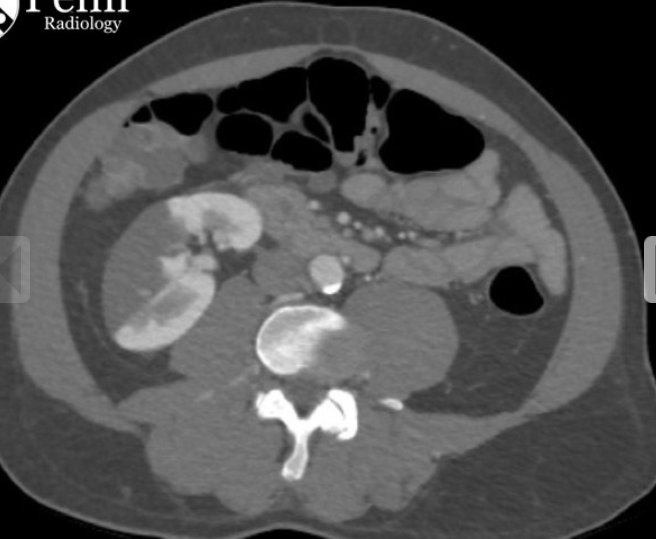

Homem, 74 anos, fibrilação atrial.

Dor abdominal aguda.

Infarto tromboembólico da artéria renal direita.

Região hipodensa com defeito de realce em forma de cunha.

Sinal do realce cortical ocorre geralmente após 24 horas do infarto e consiste no realce da margem periférica do rim na fase nefrográfica, no contexto isquemico. Ocorre em cerca de 50% dos casos.